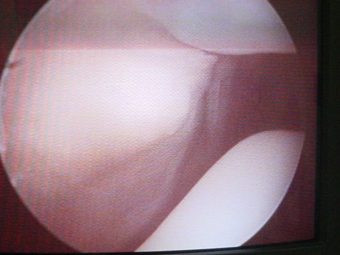

Luxación Habitual de Rótula

Envíado por Dr. Eduardo E. Martínez Melara